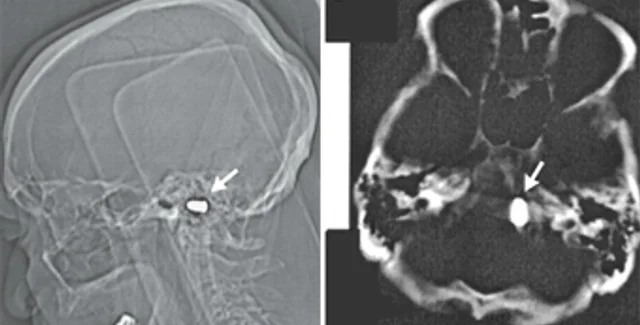

Тем не менее, сотрудники кардиоцентра доктор наук Марат Ежов, научный сотрудник отдела проблем атеросклероза Института клинической кардиологии РКНПК и ординатор этого отдела Майя Сафарова решили перестраховаться и назначили мужчине компьютерную томографию головы. Исследование показало, что у него в области большого отверстия затылочной кости находится пуля. При этом инородное тело не давило на жизненно важные органы и не вызывало опасных изменений в окружающих тканях.

Учитывая крайне низкий риск, связанный с нахождением пули в полости черепа, и пожилой возраст пациента, врачи сочли удаление инородного предмета нецелесообразным. Они лишь предупредили мужчину, что магнитно-резонансная томография головы ему противопоказана, поскольку сильное магнитное поле томографа может сместить пулю.